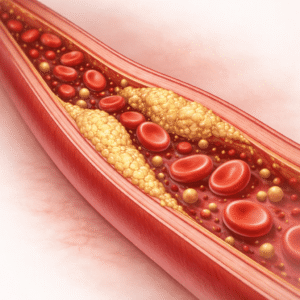

Kõrge kolesterool

Mis on kolesterooli kontroll? Kolesterool on veres rasva sarnane aine,…

Kolesterooli kontroll lihtsaks: Teaduslikult toetatud viisid kolesterooli taseme parandamiseks

Kui rääkida oma südame ja tervise kaitsmisest, mängib kolesterooli kontroll juhtivat rolli.…

Kolesterooli kontroll: Toidud, harjumused ja südame tervis

Kõrge kolesterool on peamine riskitegur südamehaiguste jaoks, kuid seda saab tõhusalt hallata.…

Kolesterooli kontroll: Toidud, harjumused ja südame tervis

Alusta küsimustikku